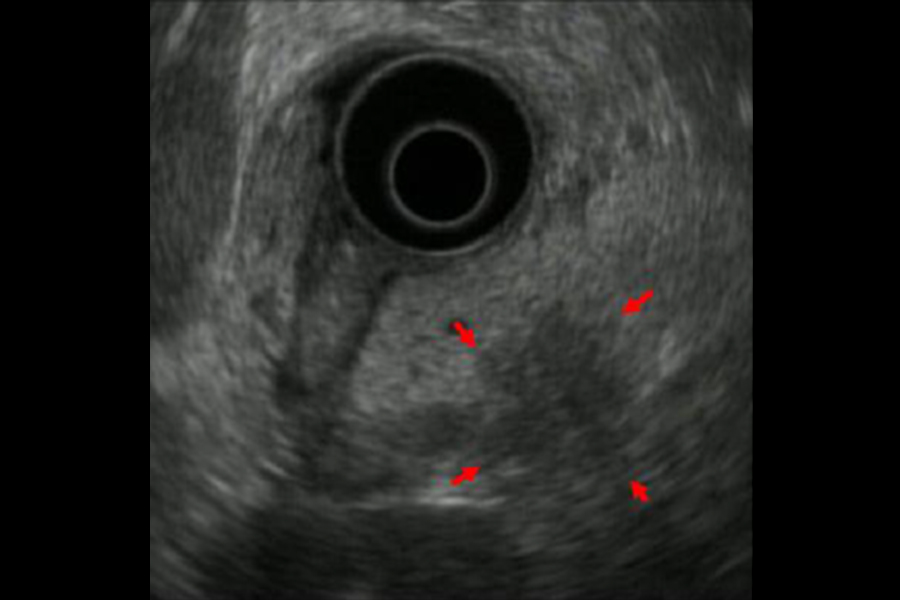

超音波内視鏡(EUS)とは、超音波装置の付いた内視鏡のことであり、“胃カメラ”と同じように口から内視鏡を挿入し、消化管の中から超音波検査を行うことで、空気の影響が少ない状態で、対象臓器・病変の近くで観察することが可能となります。そのため、体外式超音波(US)では十分な観察が難しい胆管や膵臓、通常の内視鏡では詳細がわからない消化管粘膜下病変の詳細な観察が可能であり、それらの臓器や病変に対する精密検査として行います。EUSは、小さな膵癌の描出に有効であり、今後ますます、その役割が重要になってくると考えます。

超音波内視鏡(EUS)は、胃や十二指腸の中から超音波を用いて、膵臓全体を詳細に観察することのできる検査です。我々は、膵のう胞が初めて見つかった際には、

- のう胞の詳細な評価(IPMNと他の膵のう胞性病変との鑑別、のう胞の悪性所見の有無)

- IPMNに併存することのある通常型膵癌の有無のチェック

を目的として、原則としてすべての症例にEUSを行っております。

写真は、膵のう胞(黄色矢印)を初めて指摘されてEUSを行い、膵癌(赤矢印)を診断した症例です。